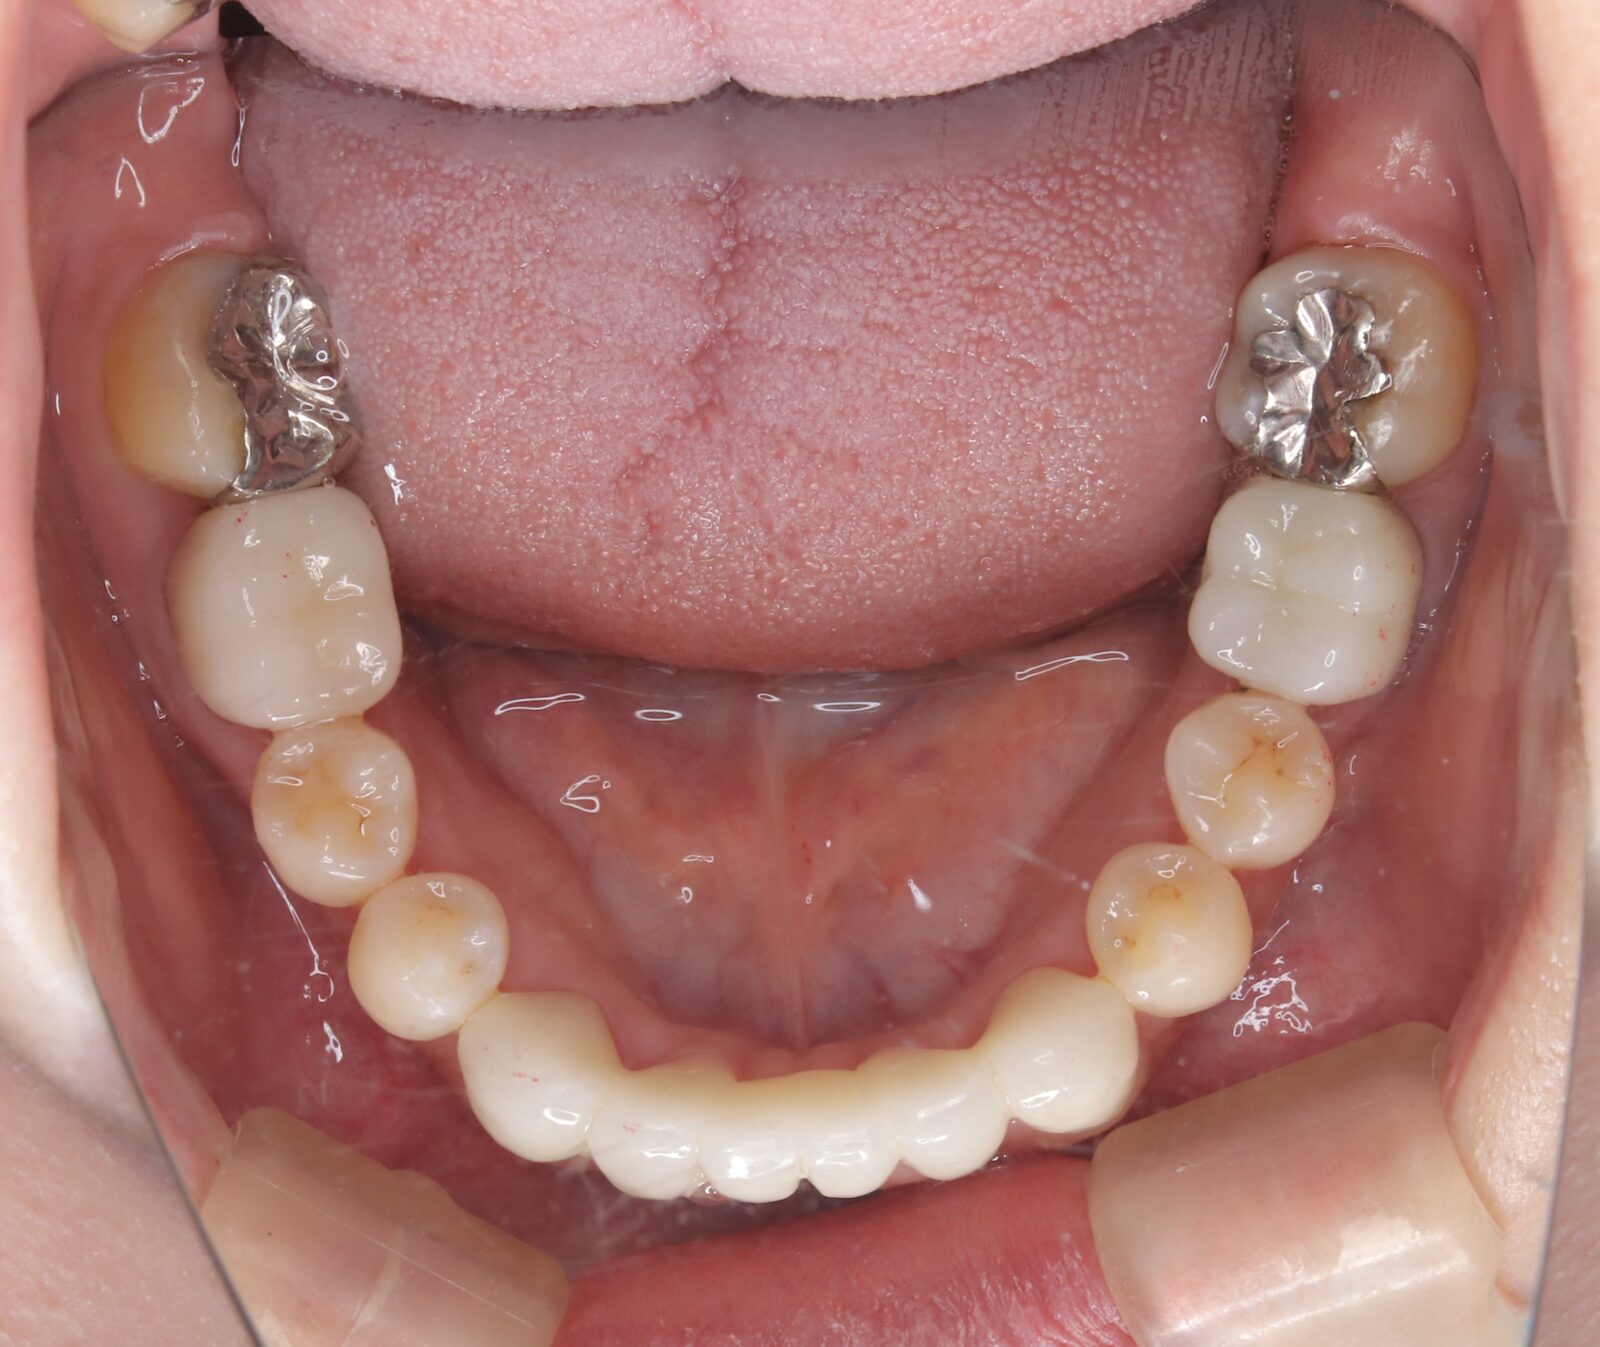

矯正後戻りを改善したキレイライン5回の症例

過去に他院でワイヤー矯正を行ったが後戻りしてしまった歯並びを改善。

・費用:230,000円(税込)

・治療期間:3ヶ月

・通院回数:4回

・27歳女性

・オプション:小臼歯の虫歯治療3本、IPR

-リスクと副作用-

・長時間マウスピースを装着するため、むし歯や歯周病のリスクがある。治療後はリテーナーを装着しないと後戻りしてしまうリスクがある。

・短期間で終了させると奥歯の噛み合わせや、全体のバランスが整わないことがある。